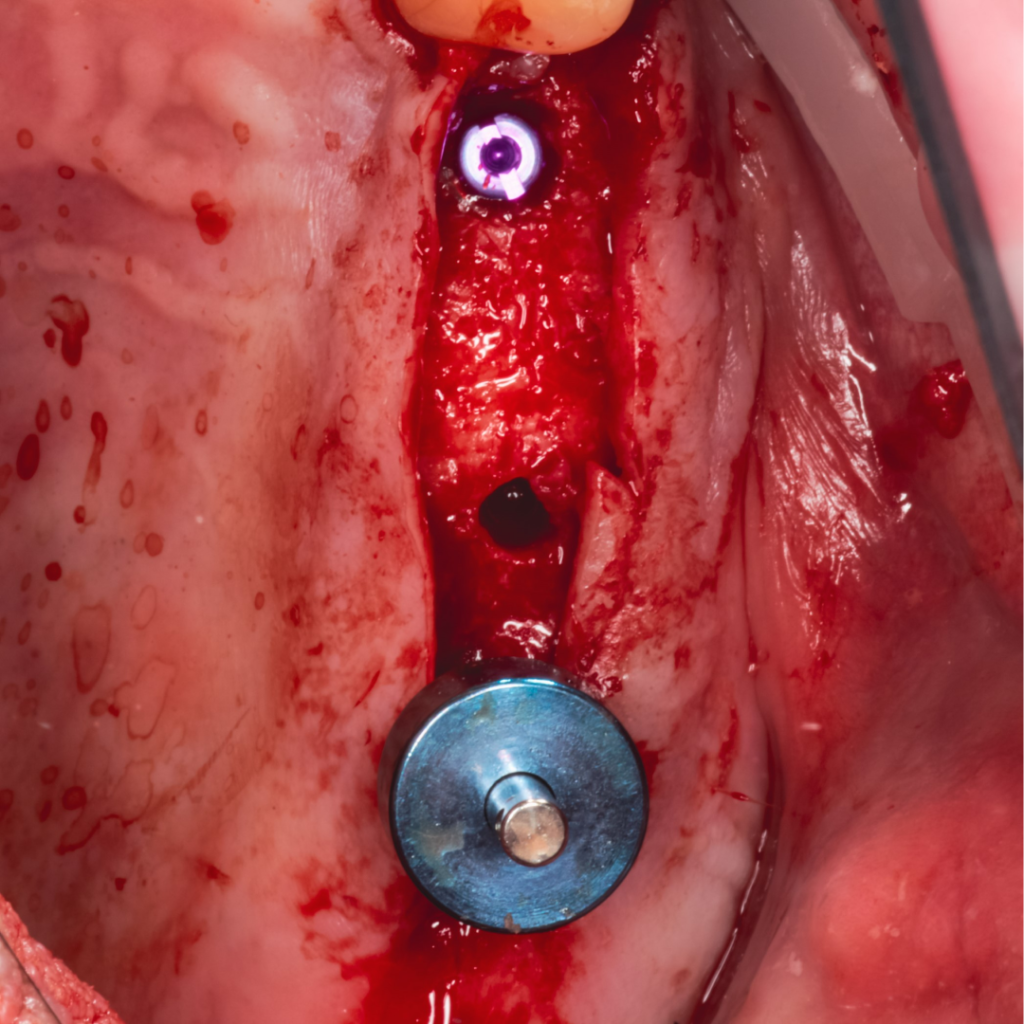

Плановая имплантация в жевательном отделе перед тотальной реабилитацией с поднятием прикуса.

По результатам диагностики принято решение установить имплантаты AnyRidge и AnyOne с использованием хирургических шаблонов Bonepen 3D.